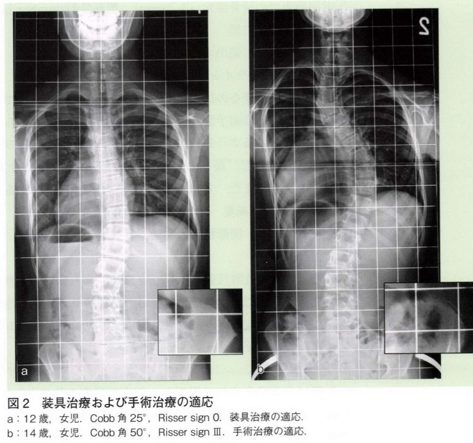

小学校や中学校の学校検診で姿勢の異常でひっかかり、当院を受診する方は比較的多いです。その中でも多い病気として胸椎や腰椎が曲がってしまう側弯症という病気があります。8割は原因が分かっていない特発性側弯症であり、女児に多いと言われています。進行すると装具治療や手術治療が必要となる方もいらっしゃいます。予防する方法はわかっていませんので、早期発見することが重要となってきます。

診察で上記の図のような肋骨隆起やウエストラインの非対称などを確認します。またレントゲンを撮像し、Cobb角を測定することで、胸椎や腰椎のカーブがあるかを確認します。

治療方法は側弯のカーブの角度によって分かれます。カーブの角度が24度以下は要経過観察の対象となり、成長段階の場合は4カ月に1度レントゲンを撮り、側弯の進行がないか確認します。角度が25度以上の場合は装具治療の適応となります。装具治療には脇下からのアンダーアームブレースが主に使用されています。

角度が45度以上で、骨が成熟している場合は手術を考えます。手術は金属製の内固定材による矯正固定術と骨移植術が中心となります。医学の進歩により矯正率は60-70%と目覚ましく上昇しております。手術の目的は、見た目の問題もありますが、最も重要なのは側弯の進行予防です。45度以上の側弯は、成長期を過ぎてからも少しずつでありますが進行することが多く、長期的には重症側弯に進行することが知られています。中高年以降で重症側弯に進行した場合、心肺機能の悪化や神経症状を生じることもあります。10歳代の段階で側弯を矯正し進行を防止することにより、将来的な健康に対する不安を払拭することが重要です。